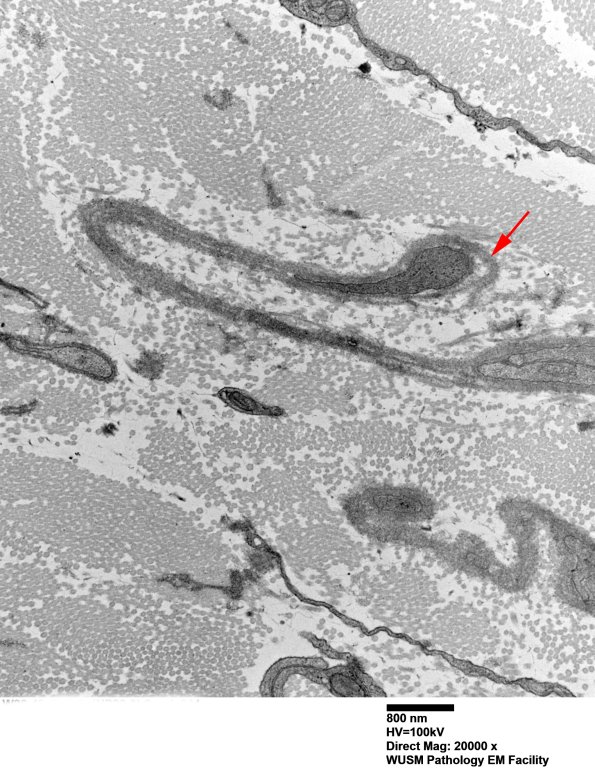

In this image the basal lamina (arrow) has partially detached from the underlying Schwann cell process. (electron micrograph)